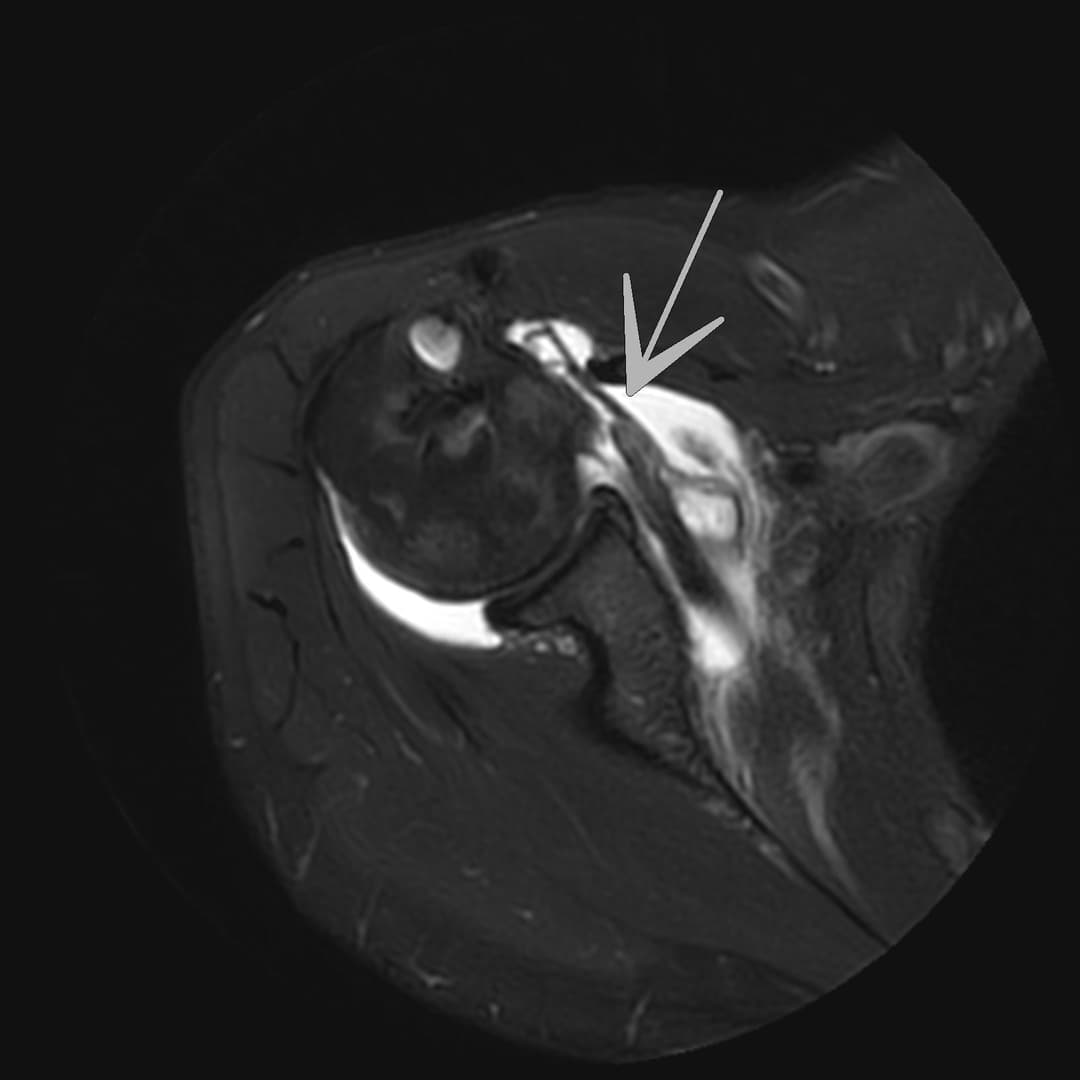

Rupture du tendon sous-scapulaire

IRM

Ténodèse du long biceps intacte. Tendons sus et sous épineux respectés. Large diffusion du contraste depuis compartiment articulaire vers la BSAD.

Rupture du tendon sous-scapulaire avec rétraction grade II-III